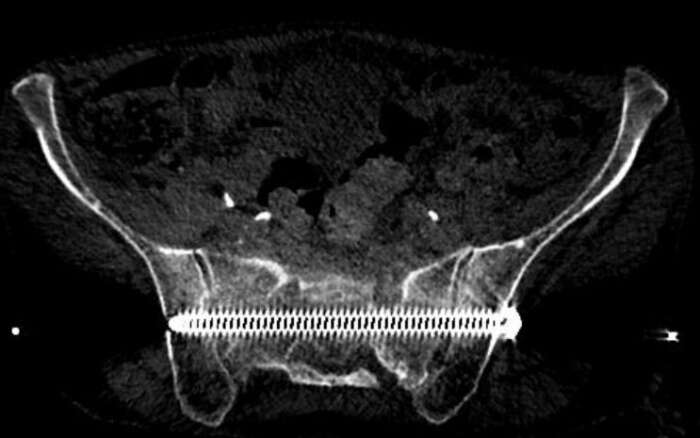

In diesem Beispiel war die Patientin vier Wochen nach einem Sturz nur noch mit Krücken und mit Schmerzen mobil. Die Computer Tomographie (CT) zeigte einen nicht verschobenen Bruch des Kreuzbeins und eine leicht verschobene Fraktur des Schambeins. Während der Operation implantierten wir CT-gesteuert zwei 7,3-mm-Schrauben. Die Schrauben gingen durch beide Ilio-Sakralgelenke und erste und zweite sakrale Wirbelkörper. Die Patientin konnte am nächsten Tag nach Hause entlassen werden und war schmerzfrei mobil.

Implantation einer 7.3 mm Schraube quer durch das Kreuzbein. Die Rückenmarks-Nerven können Millimetergenau geschont werden

Fraktur huefte 2